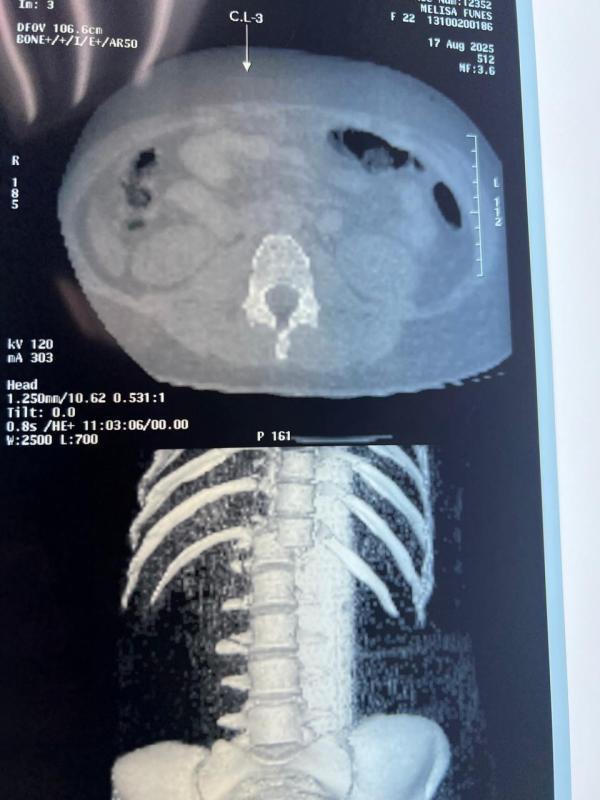

Nelsy Melissa Fúnez López es una madre soltera, de 22 años, que desde el sábado 16 de agosto se encuentra postrada en la cama de un hospital tras caerse de la rueda de Chicago en los juegos mecánicos de Santa Rosa de Copán.

López sufrió varias lesiones, entre ellas una de columna, y necesita de medio millón de lempiras para poder realizárselas.

Esta madre de un niño de cuatro años, no ha podido operarse porque presenta sangrado en uno de sus pulmones, según confirmó su madre Lilian López.